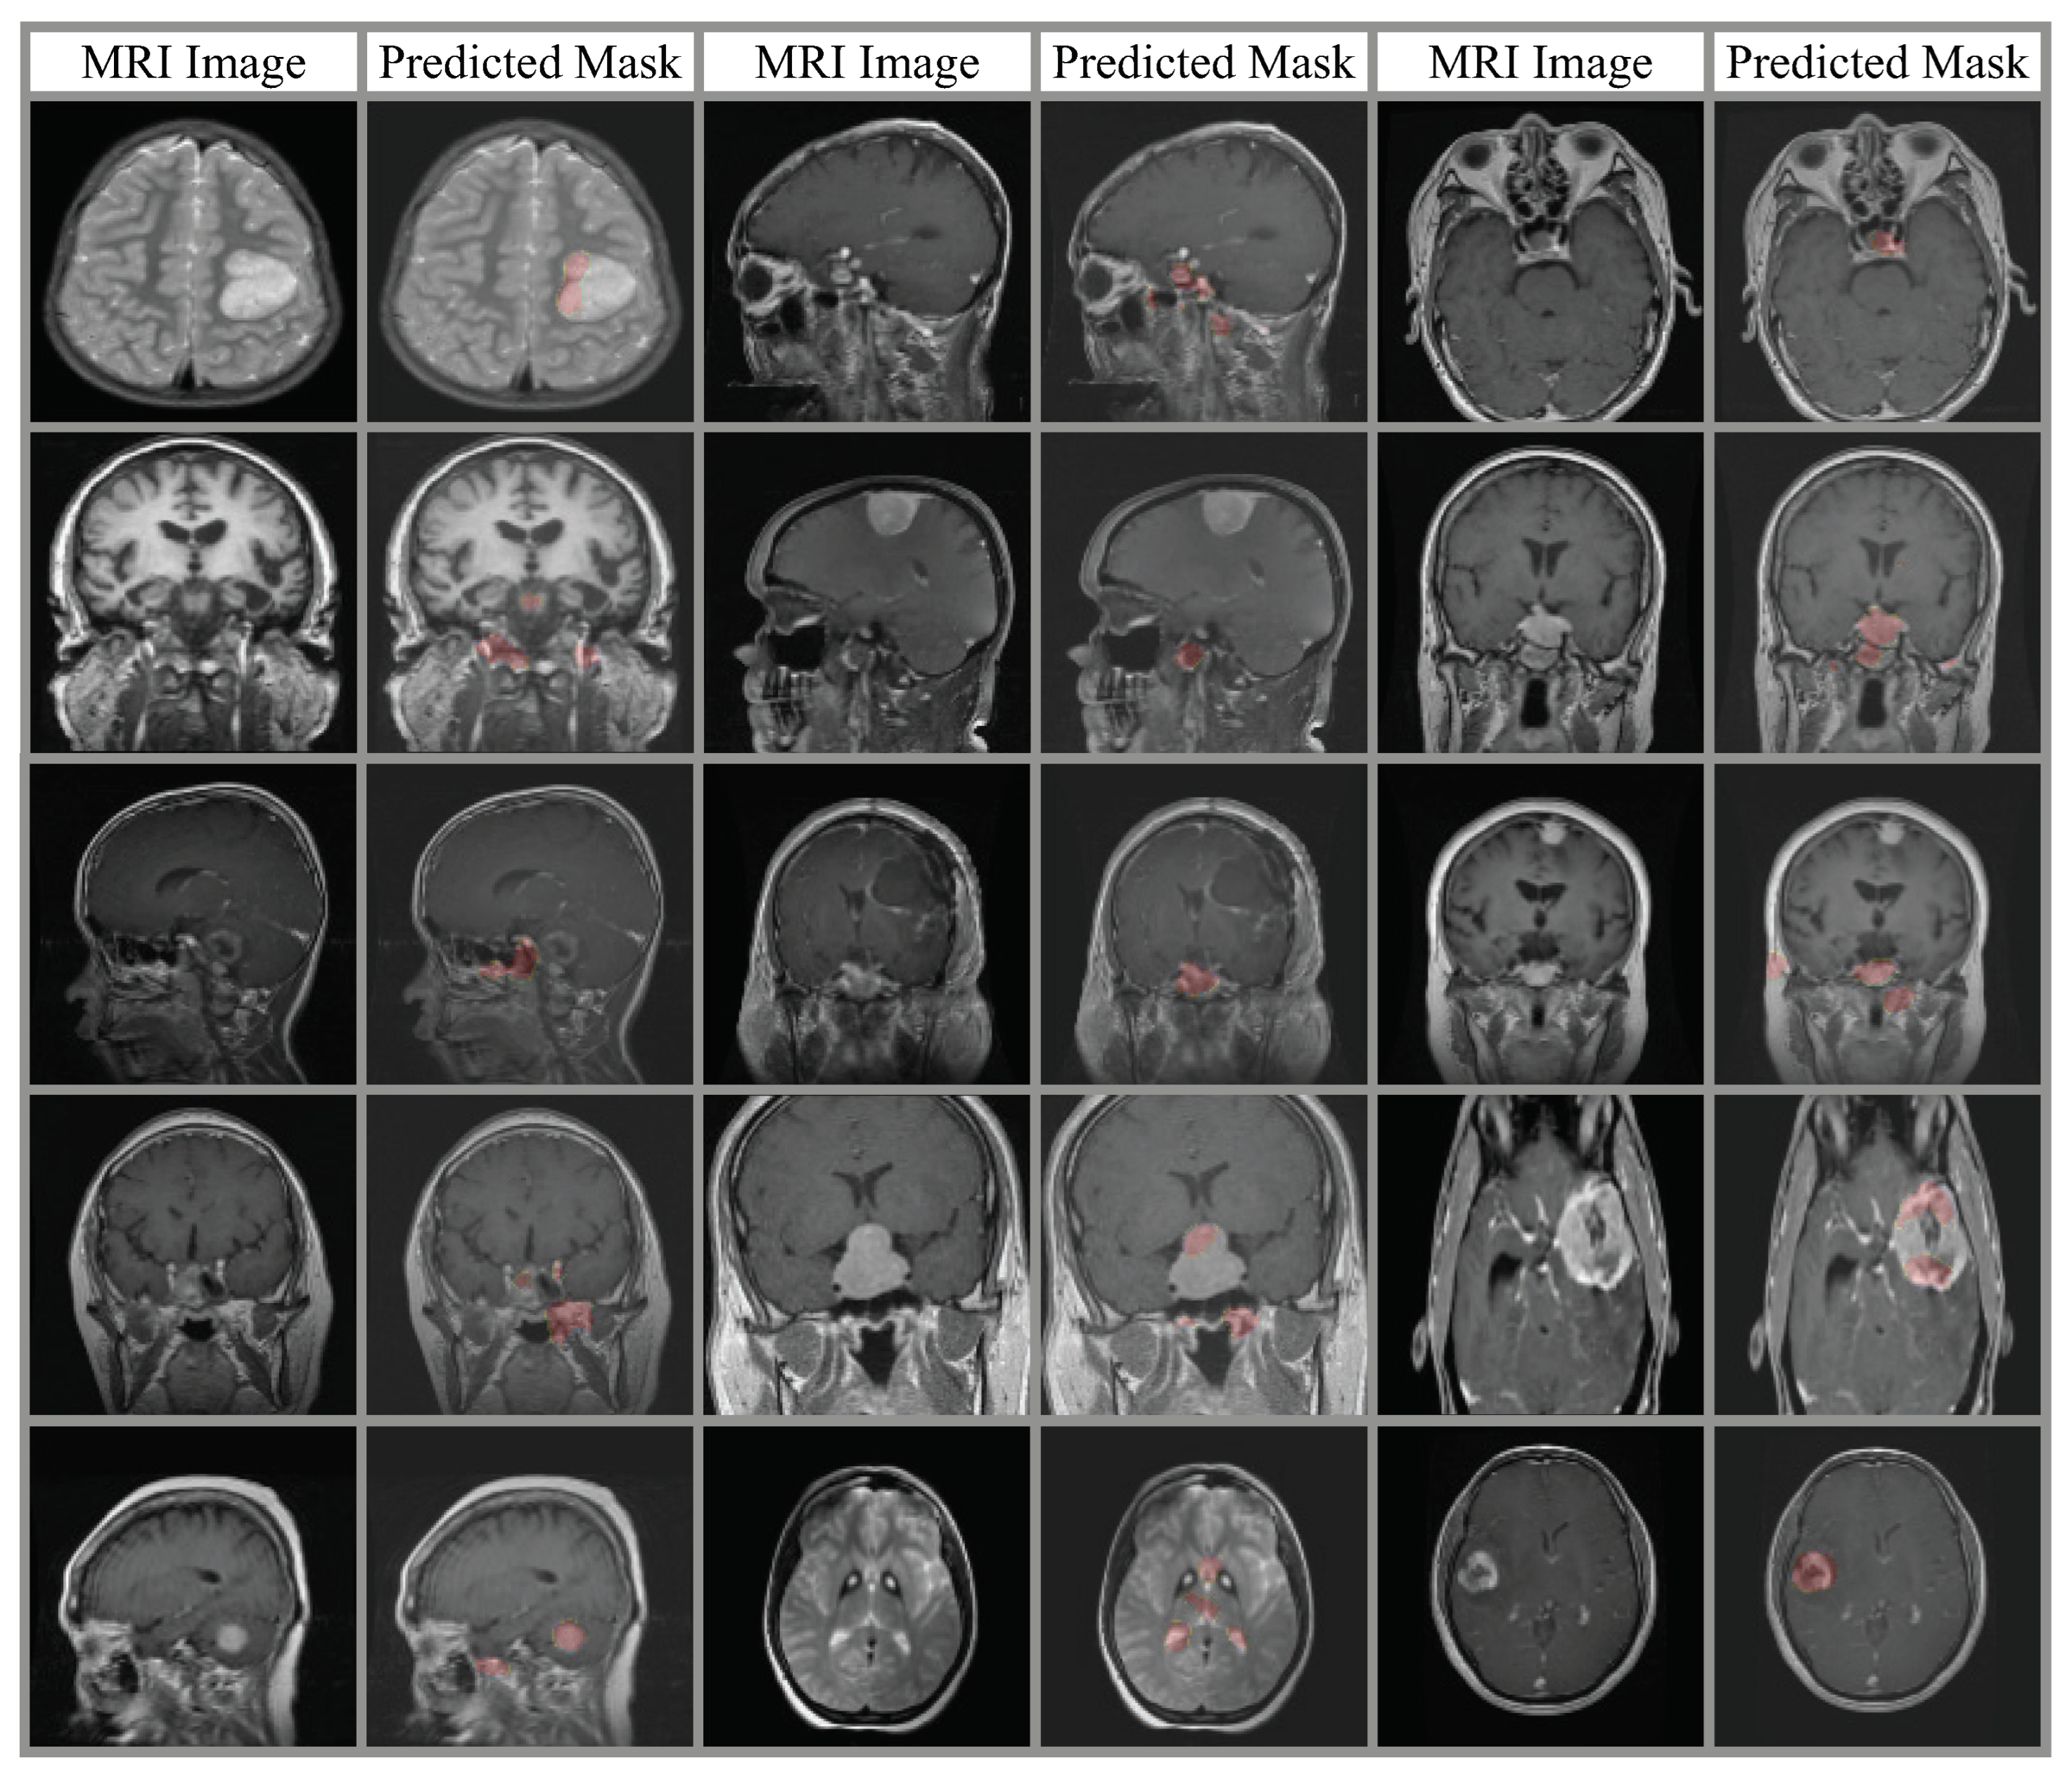

4. Experimental Results

4.2. Classification Results